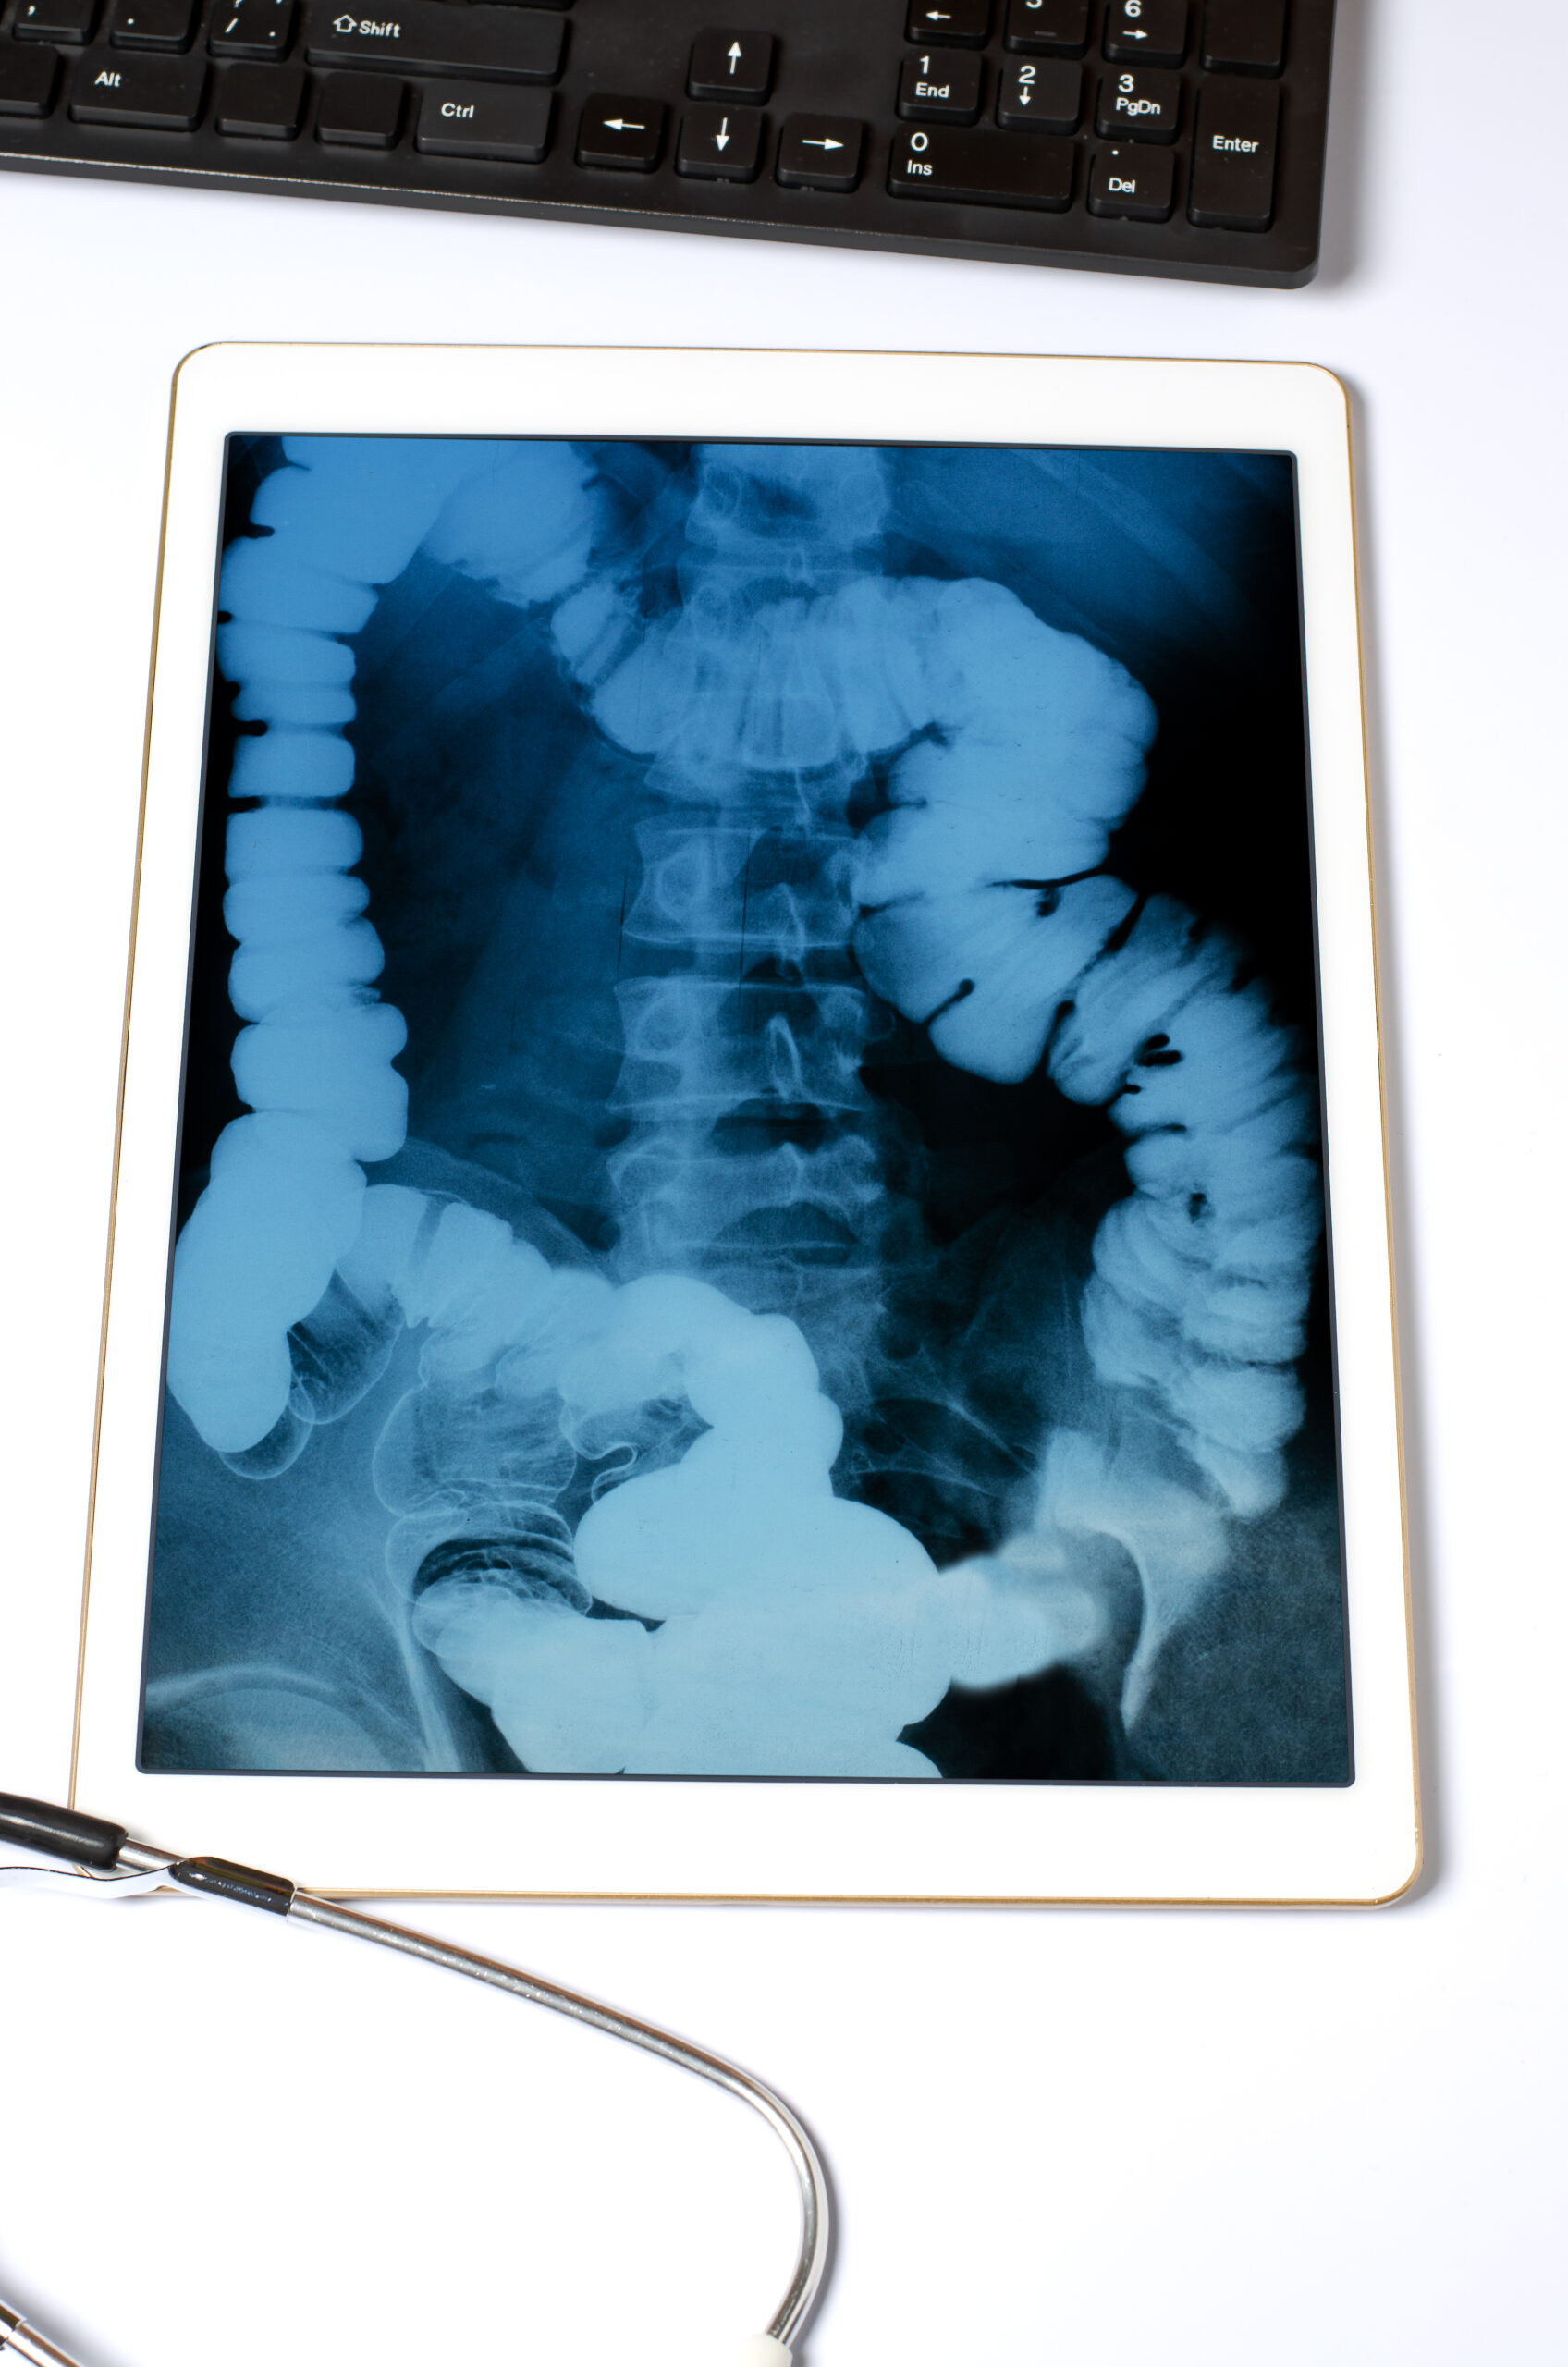

Imaging Studies – CT scan, MRI, PET-CT for tumour localization and staging